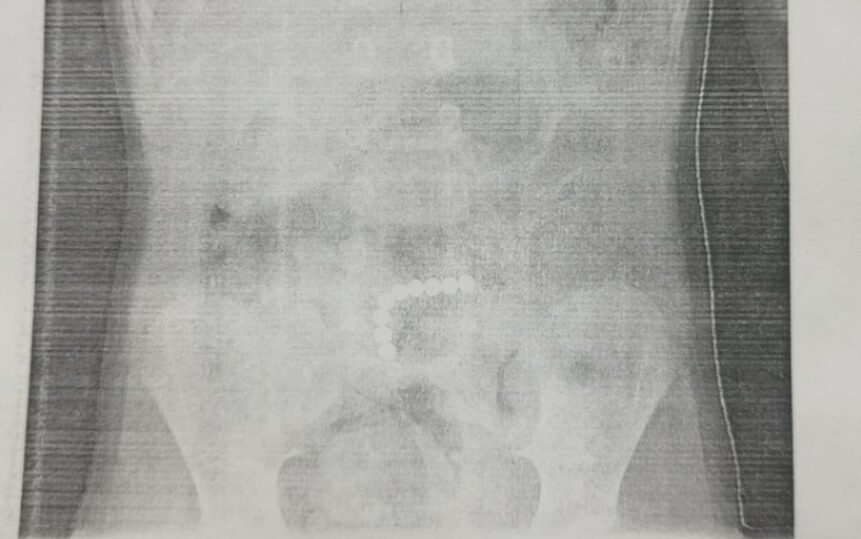

В отделение детской хирургии ребенок поступил с жалобами на рвоту и боли в животе. Сперва врачи предположили, что у малыша острый аппендицит. После узи и рентгена стало ясно, что внутри маленького пациента – инородные тела.

Потребовалась срочная операция. Магнитные шарики в пищеварительном тракте уже начали притягиваться к друг другу и повреждать стенки кишки.

На операции наш хирург Роман Черепанов и обнаружил сцепившиеся между собой магнитные шарики, которые уже спровоцировали разрывы тонкой кишки. Все 6 перфорационных отверстий врачи ушили, а магнитные шарики извлекли и удалили. Целостность и проходимость кишечника была восстановлена.